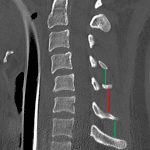

- Right C5-C6 facet joint widening with splaying of the C5 and C6 spinous processes and trace anterolisthesis of C4 on C5

- Facet joint widening without fracture

Right C5-C6 facet joint widening with splaying of the C5 and C6 spinous processes and trace anterolisthesis of C4 on C5. Findings are concerning for ligamentous injury and MRI is recommended for further assessment.